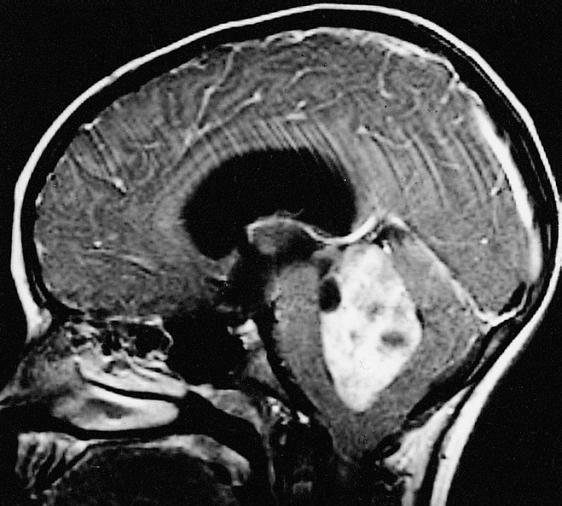

Процедуры визуализации. Магнитно-резонансная томография (МРТ) обычно применяется для постановки диагноза при опухолях головного мозга. Во время МРТ используются магнитные поля и радиоволны, которые генерируют изображение головного мозга. В некоторых случаях в вену руки вводится контрастное вещество до начала проведения МРТ. Несколько специальных изображений МРТ могут помочь врачу оценить ситуацию и назначить план лечения, включая проведение функциональной МРТ, перфузионной МРТ и магнитно-резонансной спектроскопии.